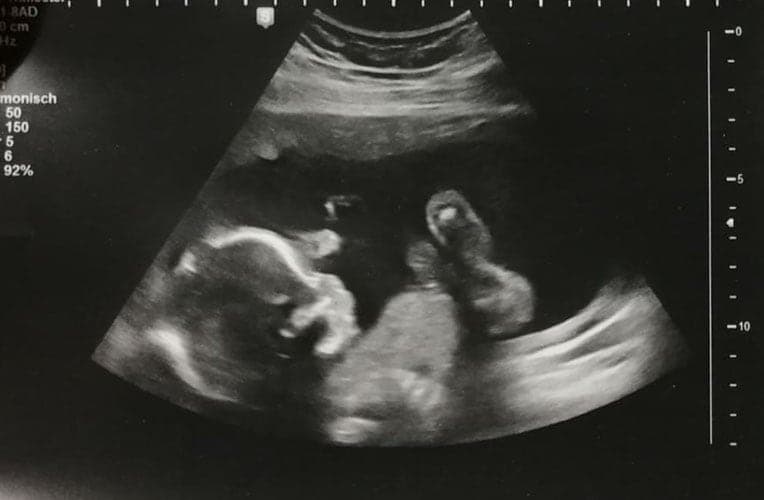

Ultraschallbilder aus dem 2. Trimester (13. bis 28. SSW)

Im 2. Trimester bekommt man oft die schönsten "Ganz-Körper" Ultraschallbilder. Das Baby ist nun so groß, dass man alles gut erkennen kann und noch nicht zu groß, so dass es noch ganz auf das Bild passt. In dieser Zeit lässt sich meist das Geschlecht bestimmen, wobei manche Babys es einfach nicht preis geben wollen und sich immer so drehen, dass man nichts erkennen kann.